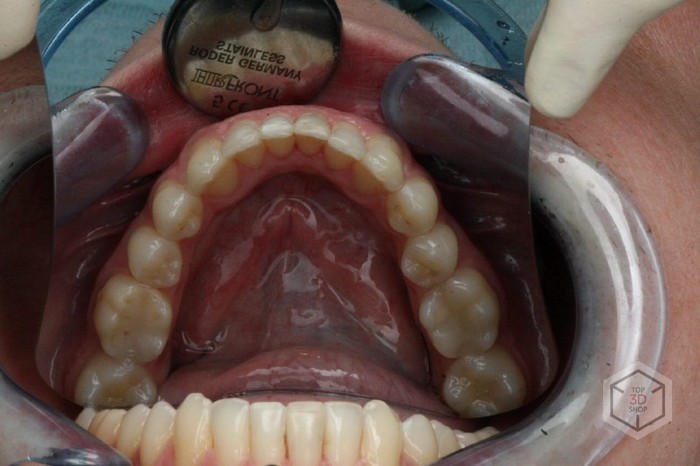

На этом снимке, кстати, он с уже надетыми элайнерами.

Далее происходит установка замков — это такие маленькие пластиковые наклейки на поверхности зубов, те самые синие штучки в планировщике, они фиксируют элайнеры и позволяют им корректно делать свое дело.

Посмотрите на результат и сравните с тем, что было.

Верхняя челюсть